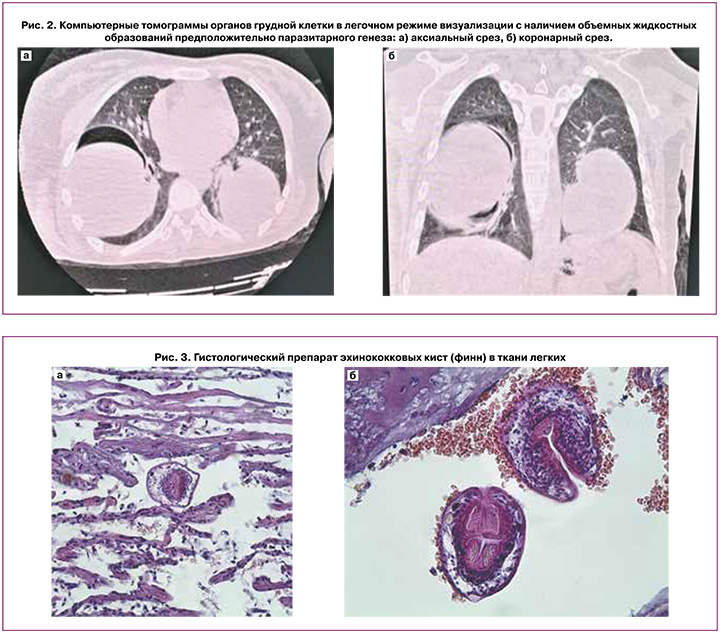

Наличие хронических заболеваний пациентка отрицала, месяц назад приехала в Российскую Федерацию из Киргизии, где проживала постоянно. Настоящая беременность – четвертая, три предыдущие беременности (5, 8 и 12 лет назад) завершились своевременными родами через естественные родовые пути, без осложнений. При поступлении в стационар состояние пациентки расценено как тяжелое, отмечались бледность кожных покровов, нарастание беспокойства и одышки. Выявлено тахипноэ (26 дыхательных движений в минуту), тахикардия (115 в минуту) на фоне нормотензии (105/70 мм рт. ст.) и нормальной температуры тела (36,5°С). При аускультации легких дыхательные шумы не проводились в нижние отделы с обеих сторон. Налажена ингаляция увлажненного кислорода через маску. Живот – мягкий, безболезненный. Матка находилась в нормальном тонусе, по размерам соответствовала гестационному сроку. Сердцебиение плода было ясным, ритмичным, с частотой 140 в минуту. При исследовании газов артериальной крови выявлены гипоксемия (pO2: 58,2 мм рт. ст., при норме 80–95 мм рт. ст.) и гипокапния (pCO2: 24,0 мм рт. ст., при норме 35–45 мм рт. ст.) с явлениями метаболического алкалоза (pH – 7,526, при норме 7,35–7,45). Данные клинического анализа крови находились в пределах физиологических значений. По результатам биохимического анализа крови обнаружено незначительное увеличение концентрации С-реактивного белка – 17,9 мг/л (при норме 0,0–5,0 мг/л). Учитывая регламент обследования пациентов с признаками дыхательной недостаточности в условиях пандемии COVID-19, выполнена КТ органов грудной клетки, при которой обнаружено наличие округлых образований в нижних долях легких размерами 118×98 мм (справа) и 88×85 мм (слева) с тонкой слоистой капсулой, жидкостным содержимым и подкапсульным расположением пузырьков газа (рис. 2). Было выдвинуто предположение, что объемные образования соответствуют наличию паразитарных кист.

После родоразрешения пациентке произведены правосторонняя и левосторонняя торакотомия и закрытая цистэктомия. Удаленные образования отправлены на гистологическое исследование, которое подтвердило эхинококковый генез поражения легких (рис. 3).